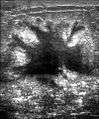

Elastography shows stiff cancer tissue on ultrasound imaging.

-

Ultrasound image shows irregular shaped mass of breast cancer.